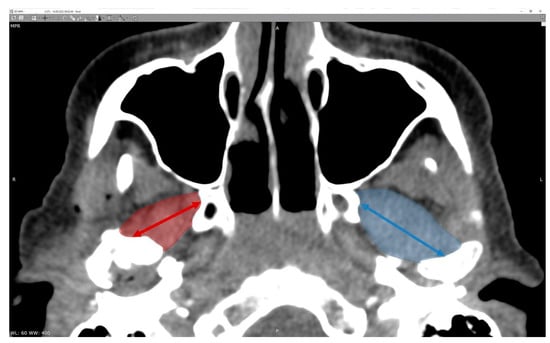

The fractured/operated side and the non-fractured/reference side were studied in both groups. The measurements of the greatest length and width of the lateral pterygoid muscle on both fractured and non-fractured sides were taken. Then, the calculation of length-to-width ratio was performed. The reference points (Figure 1) for the measurements were the center of the mandibular pterygoid fovea (pterygoid pit) and the angle between the outer surface of the lateral plate of the pterygoid processus of the sphenoid bone and the posterior wall of the maxilla. In sagittal dimension of the lateral pterygoid muscle, the measurements were made from the central point in the pterygoid depression in an axis directed to the base of the lemma (which may also correspond to the center of the palate). Measurements of the muscle size in CT images were taken at regular time intervals—just after surgery (or during the first visit after fracture in case of conservative treatment), and 3, 6, 12, and 24 months after.

Figure 1. Radiologic imaging of the reference points used for the study—broader description in the text.